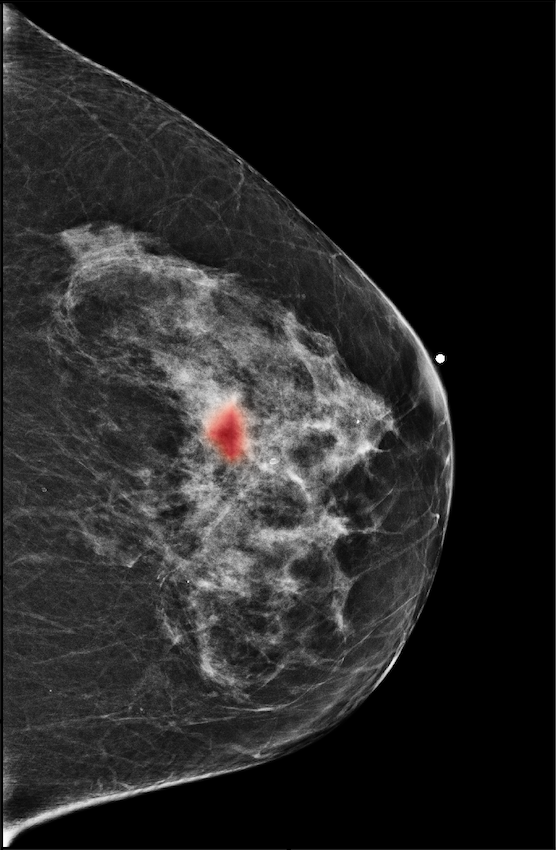

|

![]() |

| R-CC | L-CC |

| R-MLO | L-MLO |

The NYU Breast Cancer Screening Dataset [78] includes 229,426 exams (1,001,093 images) from 141,472 patients.222Our retrospective study was approved by our institutional review board and was compliant with the Health Insurance Portability and Accountability Act. Informed consent was waived. Each exam contains at least four images which correspond to the four standard views used in screening mammography: R-CC (right craniocaudal), L-CC (left craniocaudal), R-MLO (right mediolateral oblique) and L-MLO (left mediolateral oblique). An example is shown in Figure 3.

For all exams matched with biopsies, we asked a group of radiologists (provided with the corresponding pathology reports) to retrospectively indicate the location of the biopsied lesions. This way we obtained the segmentation labels: where if pixel belongs to the benign/malignant findings. An example of such a segmentation is shown in Figure 3. In all experiments (except for experiments in Section 3.6 that assess the benefits of utilizing segmentation labels), segmentation labels are only used for evaluation. We found that, according to the radiologists, approximately of exams were mammographically occult, i.e., the lesions that were biopsied were not visible on mammography, even retrospectively, and were identified using other imaging modalities: ultrasound or MRI.

In Figure 7, we visualize saliency maps for four samples selected from the test set. In the first two examples, the saliency maps are highly activated on the annotated lesions, suggesting that our model is able to detect suspicious lesions without pixel-level supervision. Moreover, the attention is highly concentrated on ROI patches that overlap with the annotated lesions. In the third example, the saliency map for benign findings identifies three abnormalities. Although only the top abnormality was escalated for biopsy and hence annotated by radiologists, the radiologist’s report confirms that the two non-biopsied findings have a high probability of benignity and a low probability of malignancy. In the fourth example, we illustrate a case when there is some level of disagreement between our model and the annotation in the dataset. The malignancy saliency map only highlights part of a large malignant lesion with segmental coarse heterogeneous calcifications. This behavior is related to the design of : a fixed pooling threshold cannot be optimal for all sizes of ROI. The impact of is further studied in 3.6. This example also illustrates that while human experts are asked to annotate the entire lesion, CNNs tend to emphasize only the most informative regions. While no benign lesion is present, the benign saliency map still highlights regions similar to that in the malignancy saliency map, but with a lower probability than the malignancy saliency map. In fact, calcifications with this morphology and distribution can also result from benign pathophysiology [42].

In addition, we observe that GMIC is able to provide meaningful localization when the lesions are hardly visible to radiologists in the image. In Figure 8, we illustrate a mammographically occult mammogram of a 59-year old patient with no family history of breast cancer and dense breasts. There is an asymmetry in the left lateral breast posterior depth which appears stable compared to prior mammograms and was determined to be benign by the reading radiologist. However, the saliency map of malignant findings successfully identifies the malignant lesion on the screening mammogram. Same day screening ultrasound (sagittal image) demonstrated a 1.2 cm irregular mass; ultrasound biopsy yielded moderate grade invasive ductal carcinoma.